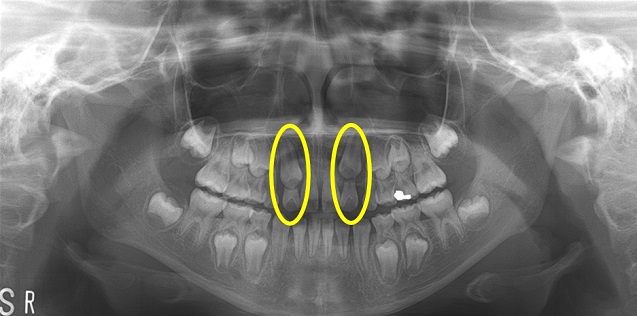

맹출장애 중 상악 견치(위턱 송곳니)와 상악 중절치(위턱 첫번째 앞니)의 매복이 가장 흔하게 나타났다.

서울대치과병원 소아치과 내원환자 분석결과에 따르면 약 4.5~9%의 환자가 영구치의 맹출장애로 인해 내원하였으며 이 중 상악 견치(위턱 송곳니)와 상악 중절치(위턱 첫번째 앞니)의 매복이 가장 흔하게 나타났다. 맹출장애로 내원한 환자 중 상악 견치의 매복을 보인 환자는 26.6%로서 가장 많은 비율을 차지했다.

상악 중절치의 맹출장애도 많이 발생하는데 유치열에서의 외상에 의한 만곡치(발육 중인 치아에서 외상이나 자리바꿈으로 인해 생기는 치아 뿌리의 기형)나 정중과잉치, 치아종 등이 원인이다.